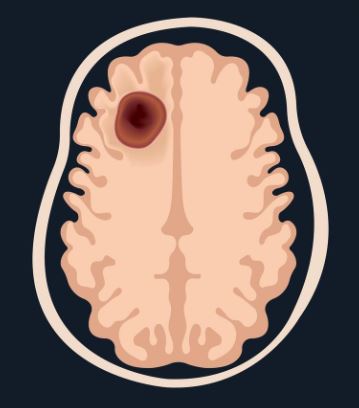

Brain tumour

A brain tumour is a lump of cells that grows in the brain and shouldn’t be there. It happens when some cells start to grow too much or in the wrong way. Some brain tumors grow very slowly and might not cause many problems, while others can grow faster and press on parts of the brain, making it harder to think, move, or feel normal. Doctors use special tests and treatments to help people with brain tumors feel better and keep the brain working well.